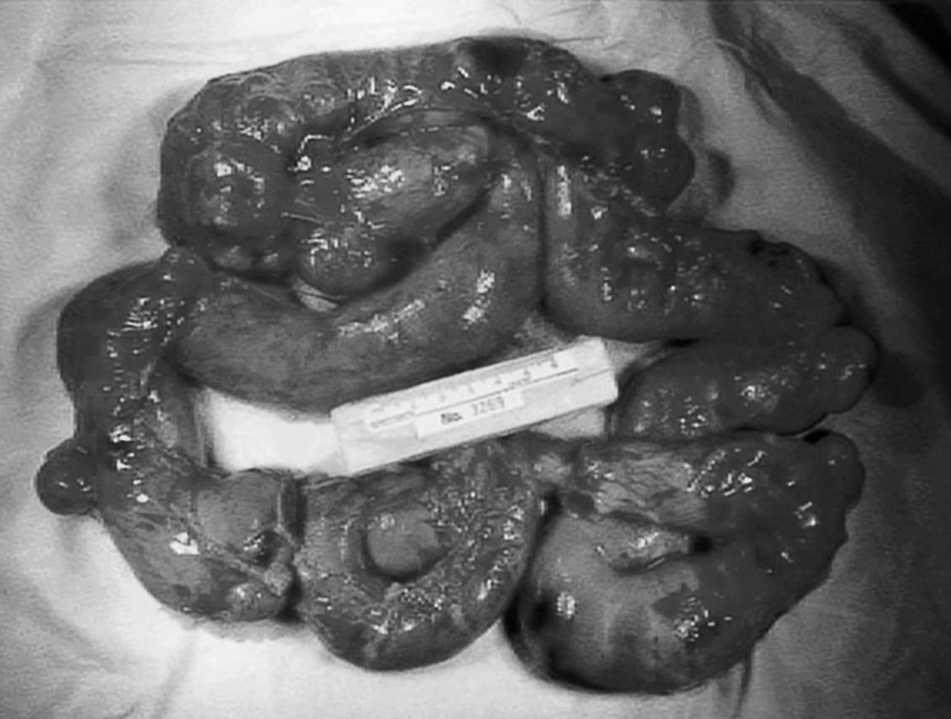

Varón de 74 años que acude a urgencias por rectorragia. En la exploración física destacaba palidez intensa, sudoración profusa, hipotensión (presión arterial [PA] de 60/40 mmHg) y taquicardia (130 lat/min). La analítica denotaba aumento de urea (96 mg/dl) con creatinina normal y anemia normocítica (hemoglobina, 6,5 g/dl; VCM 89 fl); la serie blanca y plaquetaria eran normales. Tras estabilización hemodinámica se realizaron una endoscopia alta y una colonoscopia con ileoscopia, que no fueron diagnósticas. Ante la persistencia de la rectorragia y la inestabilidad hemodinámica se realizó una enteroscopia urgente, donde se apreció gran cantidad de divertículos yeyunales, algunos de gran tamaño, con sangre fresca, por lo que se decidió realizar laparotomía urgente, que puso de manifiesto la presencia de divertículos de gran tamaño. Se procedió a la resección intestinal hasta el intestino de aspecto sano y a una anastomosis laterolateral. El estudio anatomopatológico reveló segmento de yeyuno con múltiples divertículos, algunos de gran tamaño sin poder precisar un punto de sangrado (fig. 1). El postoperatorio cursó de forma satisfactoria.

Fig. 1. Segmento de intestino delgado resecado con múltiples divertículos